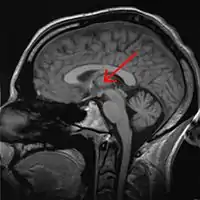

![]() Encéfalo humano mostrando la ubicación del tálamo en una RMN. Pinchado flecha roja. | ||

El núcleo reuniens es un componente del grupo nuclear medio del tálamo. En los mamíferos, está situado en la adhesión intertalámica (masa intermedia del tálamo).[1]